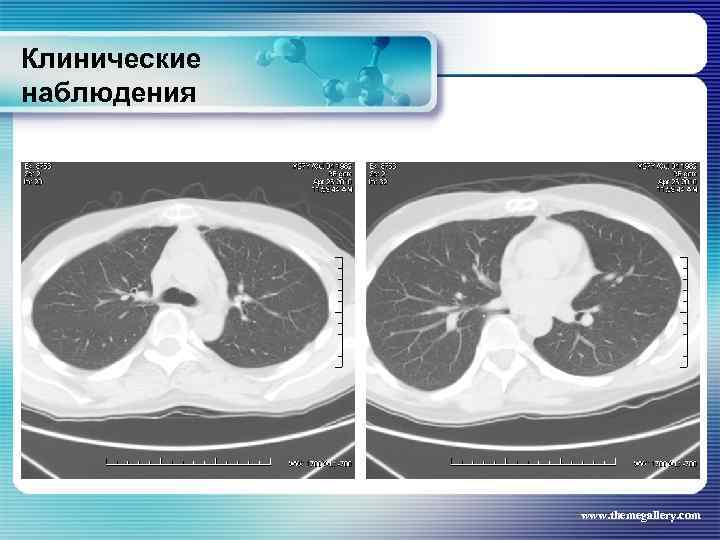

Клинические наблюдения Тот же пациент Явления пульмонита купированы на фоне терапии глюкокортикоидными препаратами www. themegallery. com

Клинические наблюдения Тот же пациент Явления пульмонита купированы на фоне терапии глюкокортикоидными препаратами www. themegallery. com